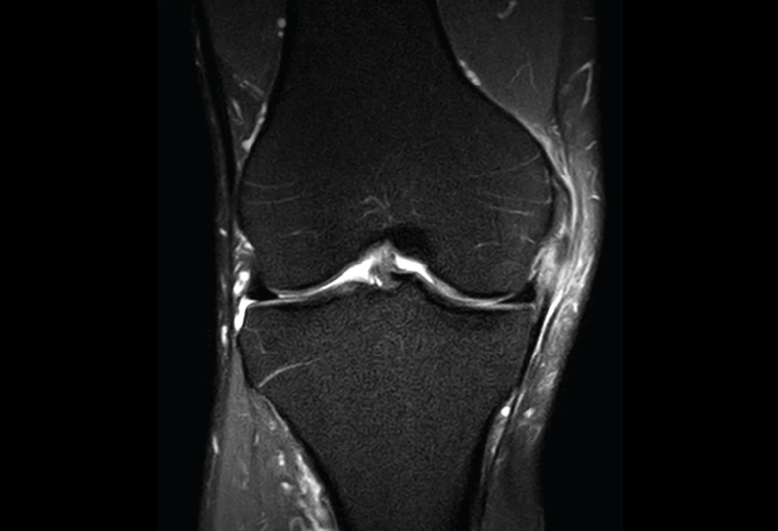

Figura 36. Corte de secuencia coronal T2 Fat-Sat: ligamentos colaterales normales.

Ligamento lateral interno (LLI) y ligamento lateral externo (LLE) (Figuras 36, 37, 38 y 39).